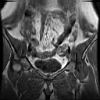

bekken